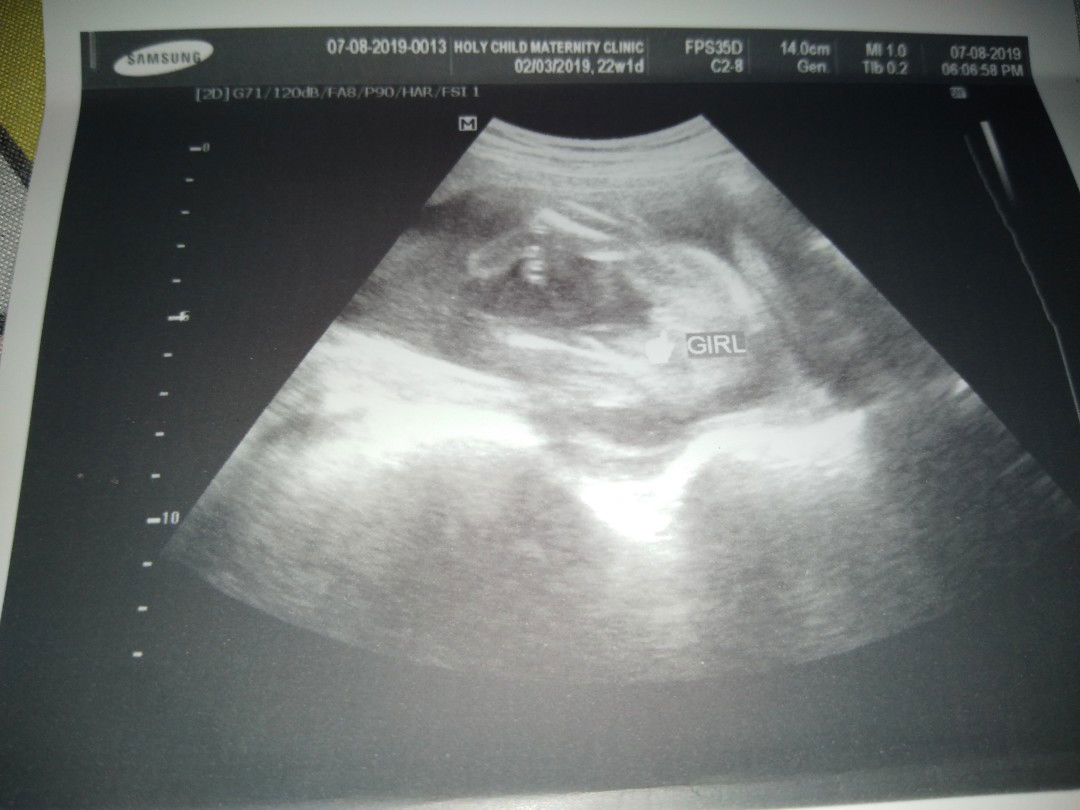

ITS A BABY GIRL! ?? Mga mommy nagpa ultrasound ako kanina sabi ng OB ko suhi daw yung baby ko. May pag asa pa kayang pumwesto si baby? 22weeks preggy napo ako.